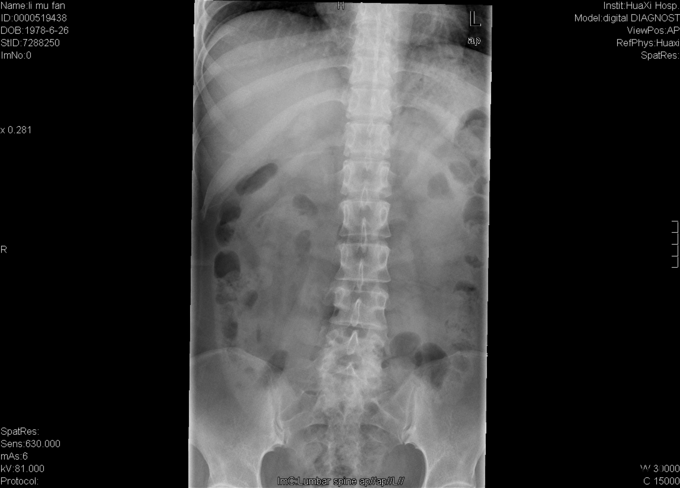

女,37岁4月,因“反复腰痛伴左下肢疼痛20+年,加重1+月”入院。20+年前患者因跌倒都出现腰部疼痛,症状反复发作,偶伴左小腿疼痛,予以牵引、针灸、按摩等治疗后症状缓解,久坐后复发。1+月前再次出现腰部及臀部疼痛,于当地医院予以对症支持后症状未完全缓解,现为求进一步治疗,遂入我院就诊。

专科检查:视:步入病房,步态无明显异常。腰椎生理弧度浅直,无明显侧弯,四肢及关节屈伸活动正常。触:脊柱腰段无明显叩痛,L4-L5、L5-S1椎旁叩痛,左臀广泛压痛,右踝外侧感觉减退,双下肢及鞍区无明显皮肤感觉减退及过敏。动量:双下肢肌力、肌张力正常,病理征(-),双侧跟腱反射正常,其他生理放射正常,余未见明确异常动量。 辅助检查:外院MRI:腰5/骶1椎间盘突出,腰5、骶1椎体异常低信号。。

初步诊断:腰5/骶1腰椎间盘突出症伴不全神经损害